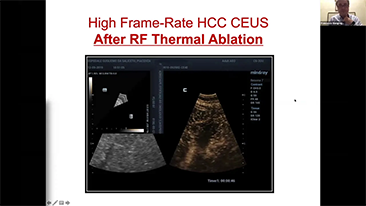

Wie deutlich k?nnen Sie eine Leber erkennen?

Bei fokalen Leberl?sionen wie H?mangiomen oder Leberkrebs spielt die Ultraschallkontrastdarstellung eine zentrale Rolle. Mit der weitreichenden nichtlinearen UWN+Kontrast-Bildgebungstechnologie k?nnen eine bessere Penetration, ein h?heres Kontrast-Gewebe-Verh?ltnis, eine geringere MI und eine l?ngere Beobachtung der Durchblutungsdauer erreicht werden.